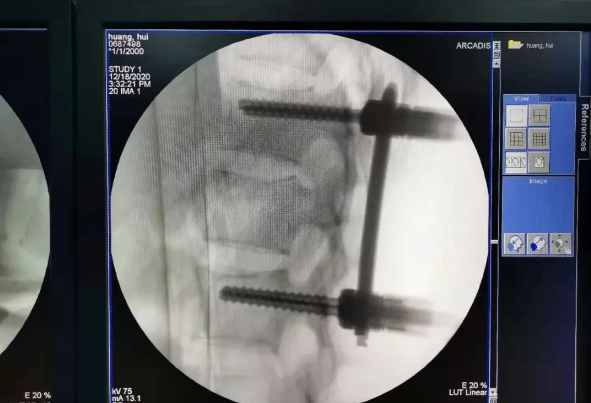

患者為22歲年輕女性,因車禍致骨盆骨折。骨盆骨折是一種復(fù)雜的創(chuàng)傷,傳統(tǒng)手術(shù)方式需要比較大的切口,而且骨盆內(nèi)有大量復(fù)雜血管和神經(jīng),手術(shù)難度和風(fēng)險(xiǎn)極大,是很多骨科醫(yī)生的禁區(qū)。

在南昌市第一醫(yī)院廖琦教授帶領(lǐng)下,由創(chuàng)傷骨科團(tuán)隊(duì)借助天璣?骨科手術(shù)機(jī)器人為患者“量身定做”最理想、最安全的教科書般的通道,完美安全微創(chuàng)完成手術(shù),并且手術(shù)時(shí)間明顯縮短,真正做到“指哪兒打哪兒”!更讓患者放心的是,天璣?骨科手術(shù)機(jī)器人的“穩(wěn)定手”機(jī)械臂進(jìn)行精準(zhǔn)定位,不用反復(fù)探尋。

由于天璣?骨科手術(shù)機(jī)器人的精準(zhǔn)及高效,可以使手術(shù)時(shí)間明顯縮短,因此在骨盆骨折手術(shù)后,在廖琦教授指導(dǎo)下,脊柱外科團(tuán)隊(duì)利用天璣?骨科手術(shù)機(jī)器人同樣為20歲女性腰椎骨折患者“量身定做”最理想、最安全的教科書般的通道,完美安全微創(chuàng)完成手術(shù),手術(shù)不僅時(shí)間縮短,并且出血和透視減少。